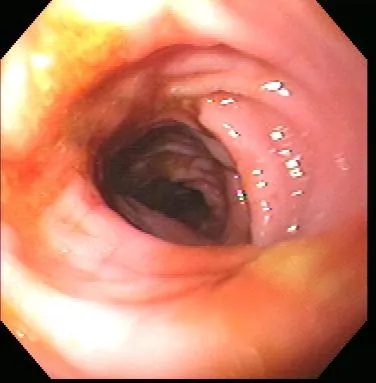

Gastroenteroscopy revealed a hard plastic foreign body (Figure 2) with curved, pointed ends. Points of the object were embedded in the gastric antral mucosa, resulting in hyperplasia. One of the curved points extended through the pylorus and hooked into the proximal duodenum (Figure 3). The endoscope could be passed around the foreign body into the duodenum, allowing biopsy of the duodenal mucosa. The gross appearance of the duodenal mucosa was normal (Figure 4). Attempts to remove the foreign body endoscopically were unsuccessful. Before the dog was sent to surgery for removal of the foreign body, colonoscopy was performed. The colon appeared normal on gross inspection (Figure 5). Biopsies were obtained from the cecum; ascending colon; transverse colon; and proximal, middle, and distal descending colon. At surgery, a gastrotomy incision was made in the pyloric antrum and the foreign body was forcefully removed. It was a plastic object used to secure the legs of a turkey carcass.

Healthy proximal duodenum

Healthy descending colon